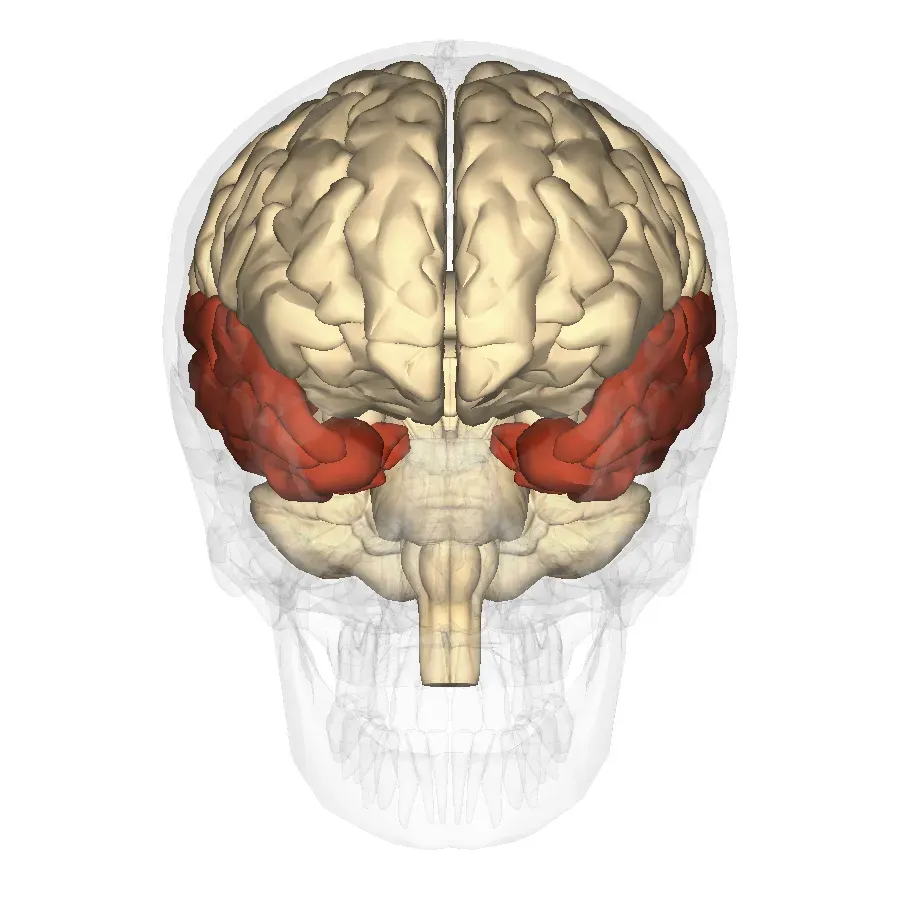

The real change came with advances in neuroscience and neuroimaging in the late twentieth and early twenty-first centuries. As MRI and EEG technologies became more precise, researchers began to link deja vu to activity in brain areas involved in memory, particularly the temporal lobes. Case studies of people with temporal lobe epilepsy proved especially revealing because many reported intense, recurring déjà vu episodes just before a seizure. When doctors mapped these events, they found that abnormal electrical activity in memory-related regions could trigger strong feelings of familiarity detached from real experiences. What had once sounded mystical now looked like an understandable, if strange, misfire in ordinary memory circuits.

To understand deja vu, it helps to picture memory not as a single filing cabinet but as a network of specialized systems. One part of the brain is especially good at storing the “what, where, and when” of events, while another handles the raw gut-sense that something is familiar. The hippocampus and surrounding medial temporal lobe structures help encode detailed episodic memories, like a birthday party or a first day at work. Meanwhile, regions such as the parahippocampal cortex act more like a familiarity detector, sending a quick yes-or-no signal about whether something has been encountered before. Deja vu appears when this familiarity signal goes rogue.